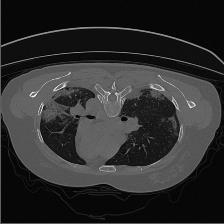

Medical image segmentation is one of the most fundamental tasks concerning medical information analysis. Various solutions have been proposed so far, including many deep learning-based techniques, such as U-Net, FC-DenseNet, etc. However, high-precision medical image segmentation remains a highly challenging task due to the existence of inherent magnification and distortion in medical images as well as the presence of lesions with similar density to normal tissues. In this paper, we propose TFCNs (Transformers for Fully Convolutional denseNets) to tackle the problem by introducing ResLinear-Transformer (RL-Transformer) and Convolutional Linear Attention Block (CLAB) to FC-DenseNet. TFCNs is not only able to utilize more latent information from the CT images for feature extraction, but also can capture and disseminate semantic features and filter non-semantic features more effectively through the CLAB module. Our experimental results show that TFCNs can achieve state-of-the-art performance with dice scores of 83.72\% on the Synapse dataset. In addition, we evaluate the robustness of TFCNs for lesion area effects on the COVID-19 public datasets. The Python code will be made publicly available on https://github.com/HUANGLIZI/TFCNs.

翻译:医学图像分解是医学信息分析的最根本任务之一,到目前为止已经提出了各种解决办法,包括许多深层次的学习技术,如U-Net、FC-DenseNet等。 然而,高精度医学图像分解由于医疗图像中存在固有的放大和扭曲,以及存在与正常组织密度相似的损伤,因此仍是一项极具挑战性的任务。在本文件中,我们建议TFCN(全面革命稠密网络的传输者)通过向FC-DenseNet引进ResLear-Transerferent(R-Transerfor)和Culvacial线性关注区(CLAB)来解决这一问题。TFCN不仅能够利用CT图像中更多的潜在信息来提取特征,而且还能够通过CLAB模块更有效地捕捉和传播语性特征和过滤非神经性特征。我们的实验结果表明,TFCN可以在Syapseion/SymblyDDS上以83CN-72 ⁇ 的分数实现状态。此外,我们在Synapse-DRIS数据设置上,我们还将评估CUTFTFI/LIS的可靠度。